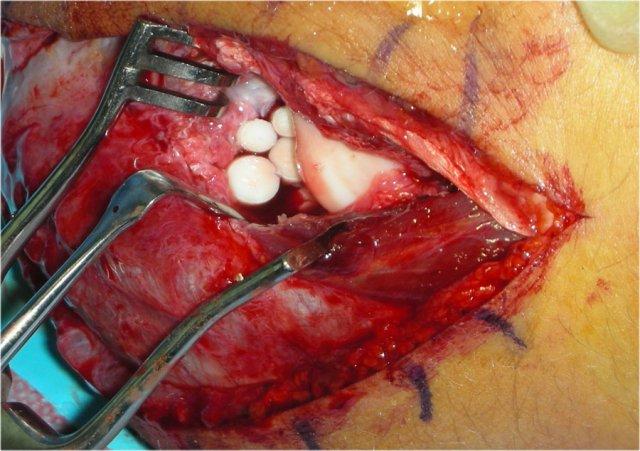

OATS procedure

OATS là viết tắt của ghép xương sụn tự thân (osteochondral autologous transfer).

Các mảnh sụn và xương được lấy từ một vị trí xương khác không chịu lực và chuyển đến chỏm con (capitellum).

Ở bệnh nhân này, sụn được lấy từ phần không chịu lực của khớp gối.

Sau đó, các lỗ được khoan vào chỏm con và các khuyết hổng được lấp đầy bằng xương và sụn tự thân.

Ở đây, lỗ khoan trên chỏm con được lấp đầy bằng bốn mảnh xương và sụn.

The radial head is seen opposite the capitellum.